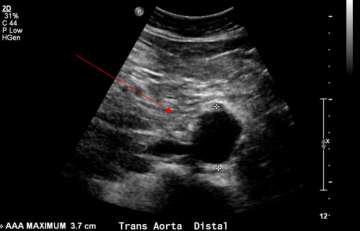

Abdominal aortic aneurysm (AAA) is an enlargement of the aorta, which can be detected by a screening ultrasound examination. Abdominal aortic aneurysms can be commonly asymptomatic and can be silently unnoticed for many years. Continued growth beyond a certain size carries risk of fatal rupture which is a life-threatening medical emergency. Early detection with a AAA screening ultrasound has been linked to lower rates of rupture and deaths.

A quick, painless, noninvasive ultrasound examination of the abdomen detects if the diameter of the abdominal aorta is greater than 3.0 cm.